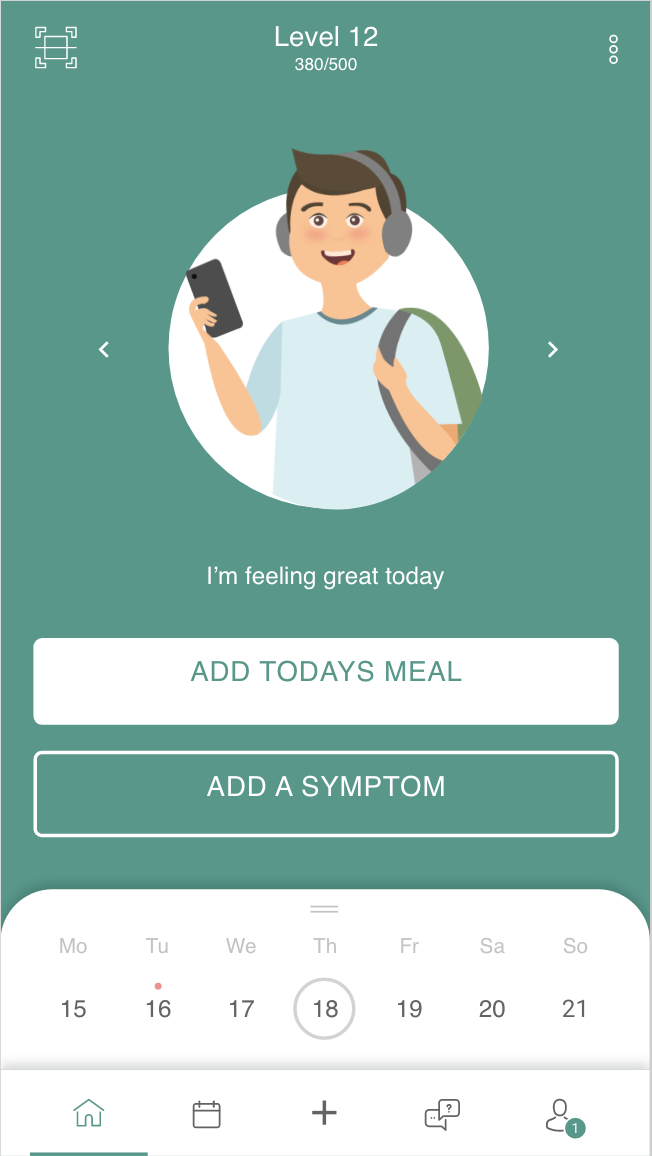

Patientube

1

Interface- and Interactiondesign

8

Interface-and Interactiondesign 2

14